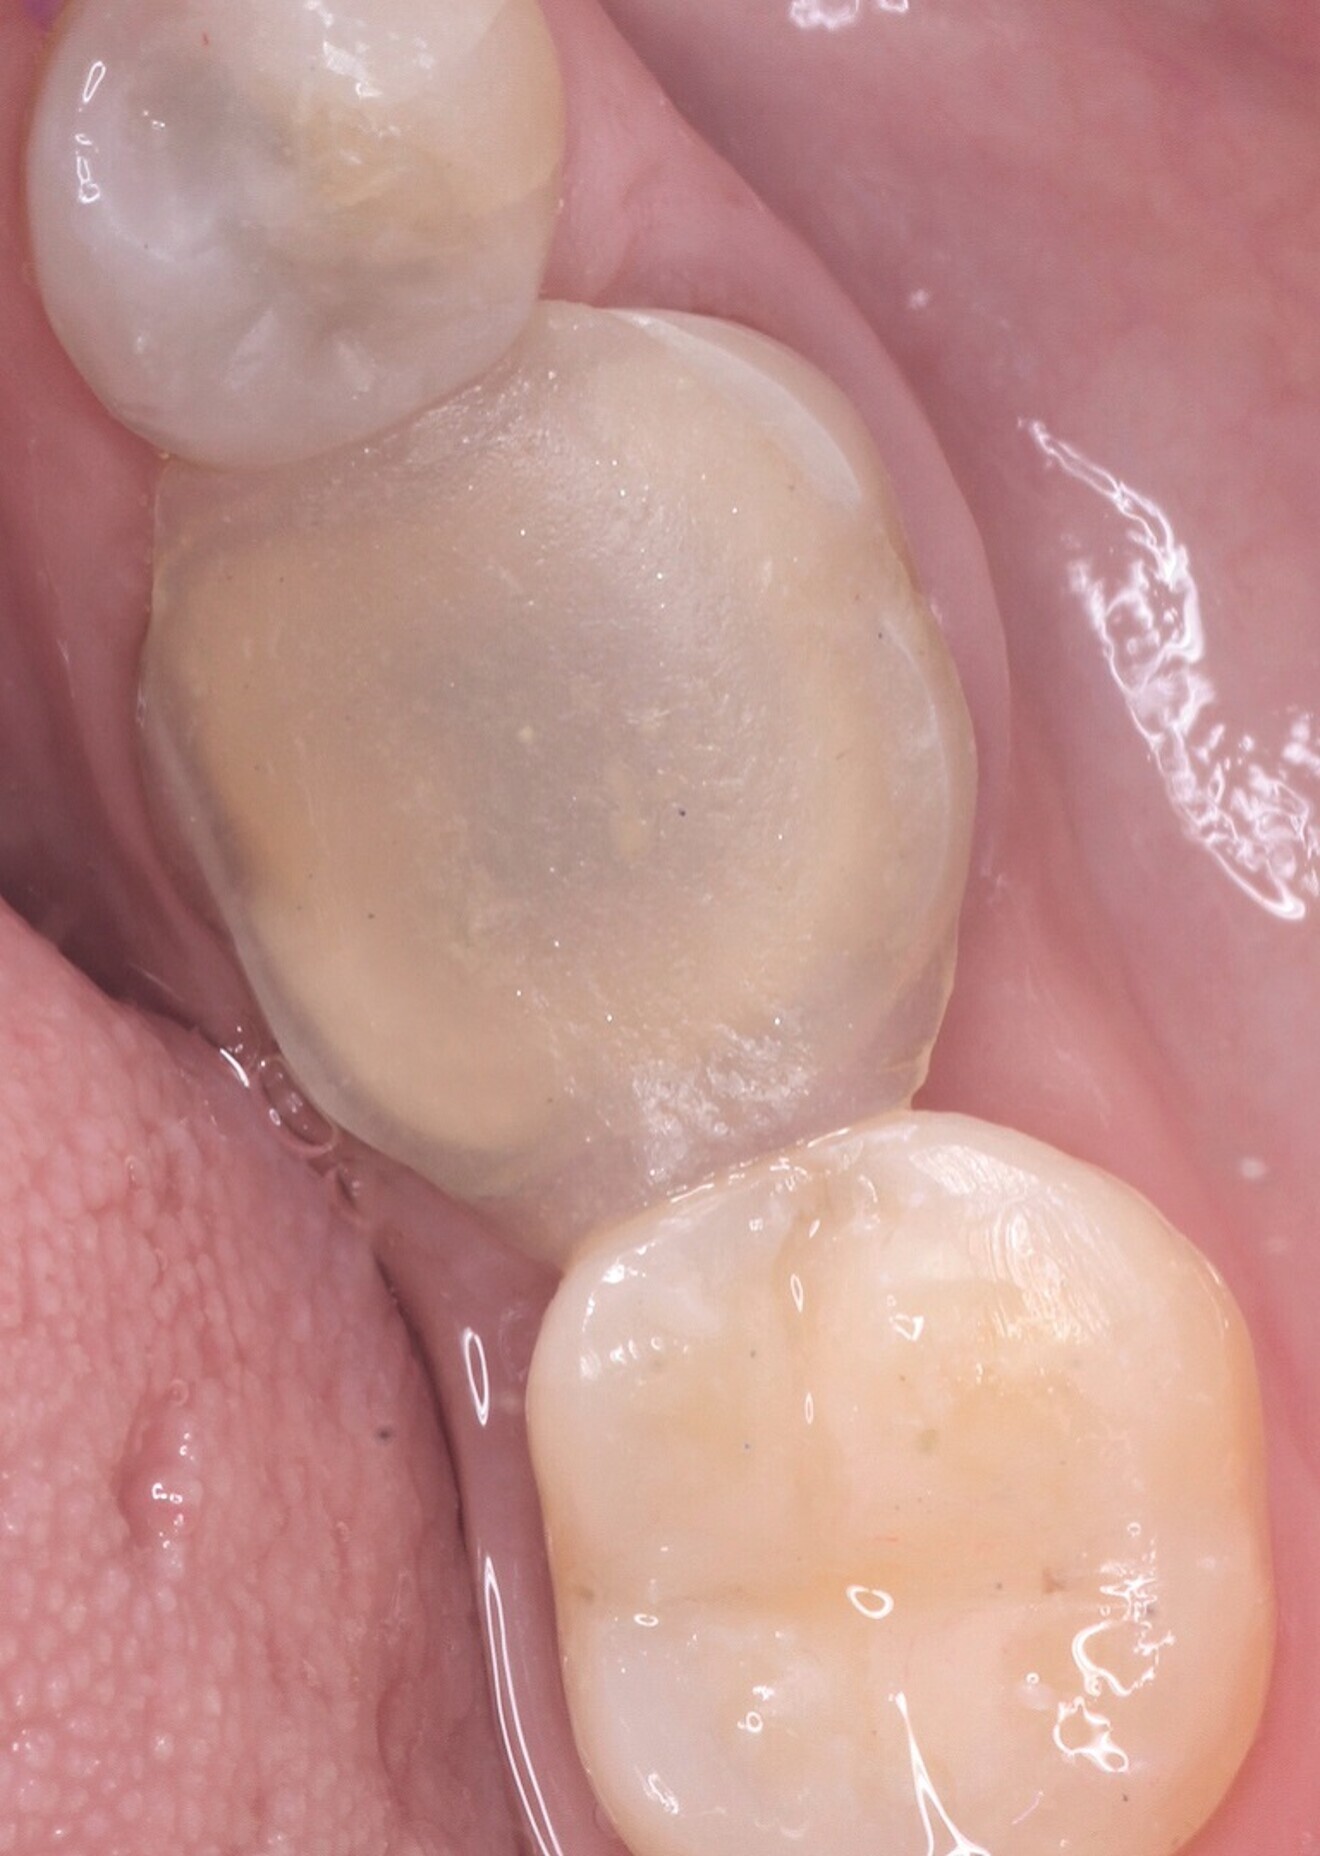

Fig. 1: Initial situation: failure of periodontal anatomical integrity due to overcontoured amalgam filling in tooth #45, and cracked and lost amalgam on tooth #46. (All images: Lucas J. Echandia & Martin I. Ibañez)

The clinical examination revealed an amalgam filling over the asymptomatic root of tooth #46 and the overcontoured amalgam filling in tooth #45, which had facilitated inflammatory and hyperplastic changes to the surrounding gingival margin, and tooth #46 had lost several coronal areas of the residual hard tissue and most of its lingual wall and presented with some microcracks on the residual surface (Fig. 1). Tooth #45 did not show any clinical symptoms on the pulp vitality test.